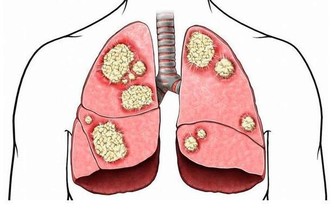

10. 癌症

如果腰痛不能精確定位,可能是由於內臟癌症,如胰腺、十二指腸、結腸、子宮、子宮頸和卵巢等。其症狀就包括背部疼痛,即使充分休息也不能緩解,並且夜間疼得最厲害。這種非機械性的背部疼痛,若藥物治療和姿勢改善都不能使其好轉,就需要去看醫生了。